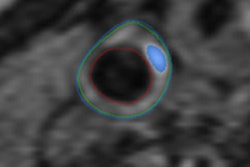

Histological features associated with lipid/necrotic core

|